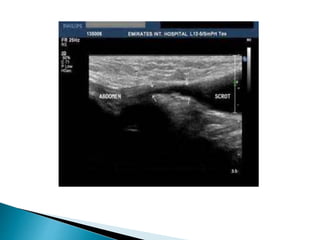

 Majority of prepubertal males

 Most commonly lies in the inguinal canal

Ultrasound first line investigation

 Located within inguinal canal

 May be normal or atrophic